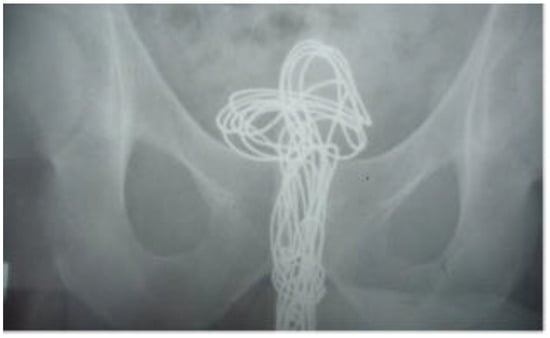

| 1 | 34 | M | wire | urinary bladder | unknown | unknown | hematuria | cystotomy |

| 3 | 32 | M | string | urinary bladder | alcohol | 3 years | hematuria | cystotomy |